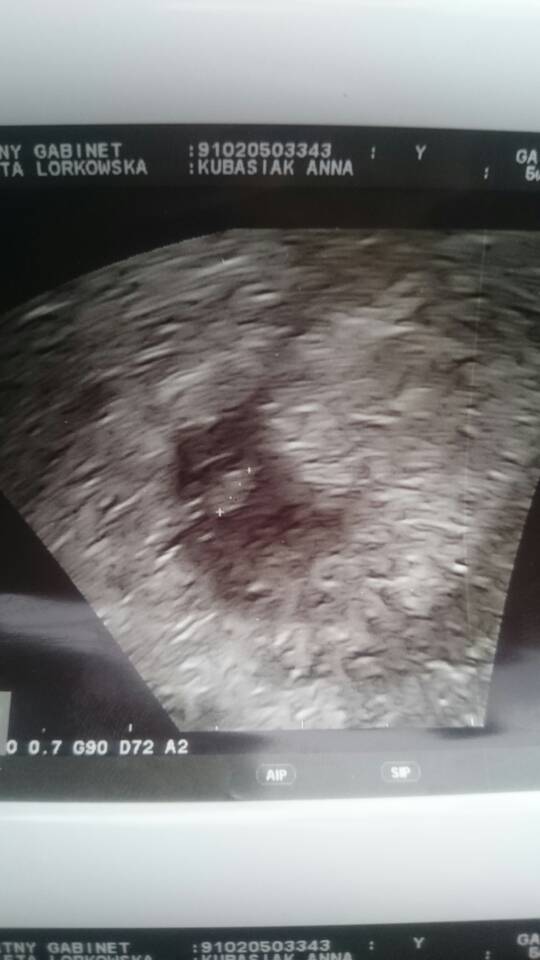

Kazała mi przyjść za dwa tyg. Mówiła że jeszcze młoda ciąża i wszytko może się zmienić ale dała mi do zrozumienia że źle to widzi. ;( mówiła już ze u niektórych widzi puls, a tu nie widzi. ze możliwe że płód jest uszkodzony i dlatego leków nie da że przy takim pęcherzyku TYLKO CZEKANIE